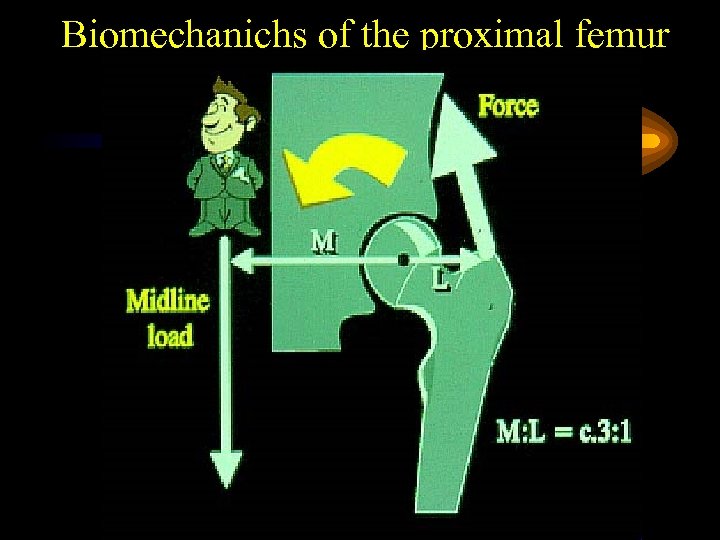

Biomechanichs of the proximal femur

Biomechanichs of the proximal femur

Biomechanichs of the proximal femur

Biomechanichs of the proximal femur

Biomechanichs of the proximal femur

Biomechanichs of the proximal femur